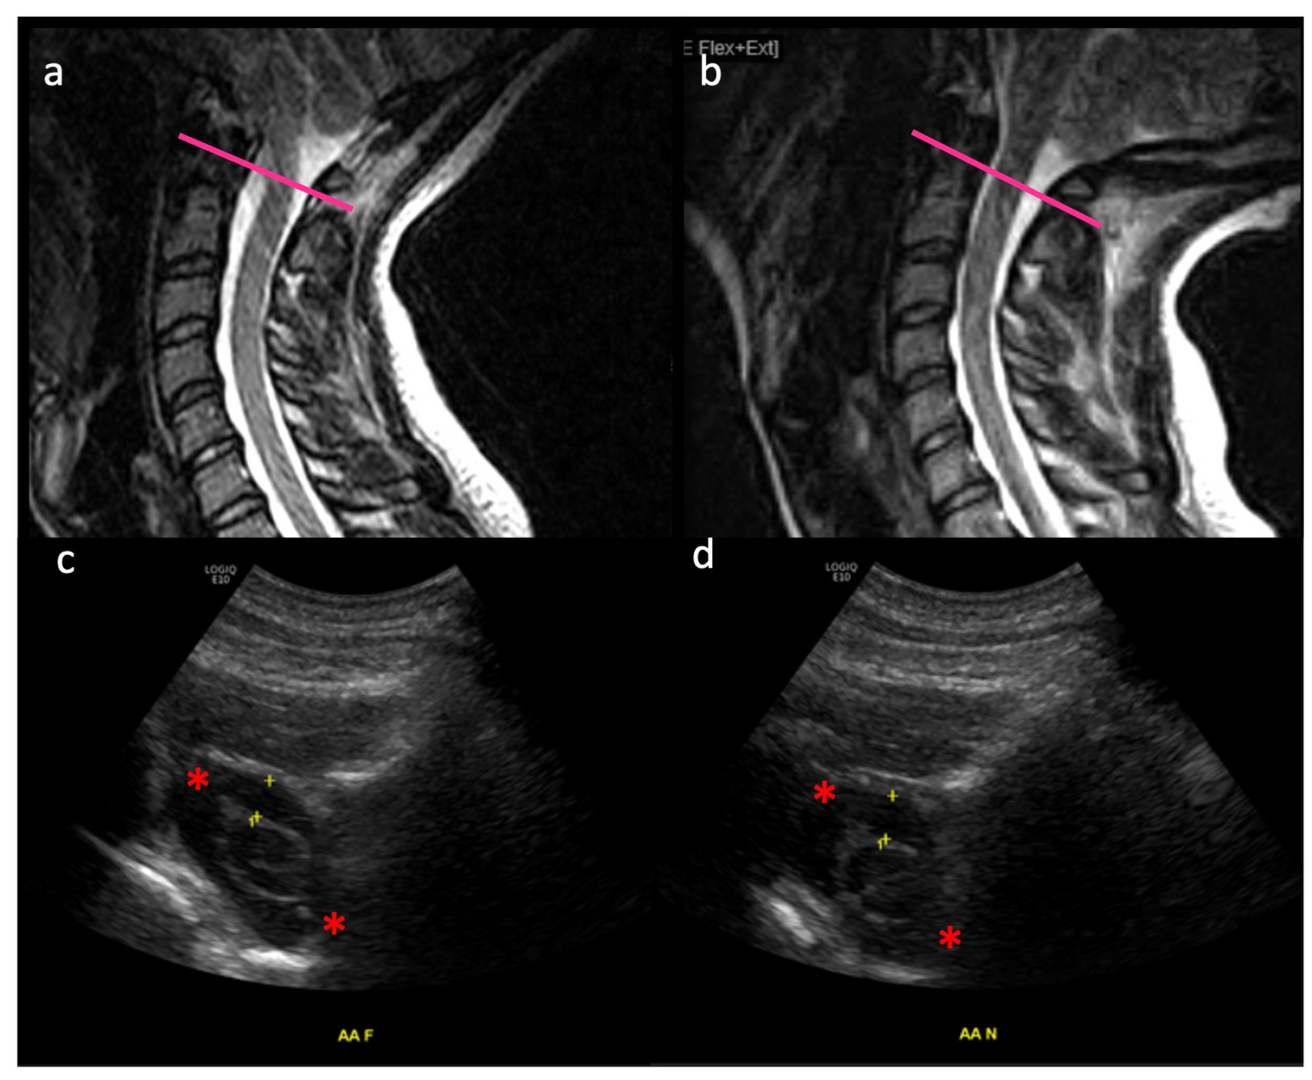

| Figure 4, Figure 5, Video S1 | 10F | Mix of suboccipital headaches and “migraine” type frontal headaches refractory to medical management and physical therapy, light sensitivity | 1 year | 7.5 mm tonsillar herniation | N | Gradual resolution of preoperative headaches over the course of 1year post surgery |

| Figure 5 | 47F | Valsalva induced headaches, neck pain, episodic vergigo and dizzines, difficulty swallowing, fatigue and cognitive slowing with brain fog, co-morbiditie of hypermobile Ehlers-Danlos-Syndrome and tethered cord syndrome | 3 years | 5.8 mm tonsillar herniation | Y | Headaches and preoperative dizziness gradually improved, residul back and leg pain required tethered cord release 6 months post Chiari decompression, stable syrinx |